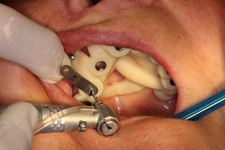

Principem řízené navigace pomocí chirurgických šablon je pasivní vedení zahlubovacích a rozšiřovacích vrtáčků do čelistní kosti na základě předem naplánované přesné pozice, směru, sklonu a hloubce jednoho nebo více implantátů.

Chirurgicko-protetický plán vychází z 3D rentgenu čelisti, otisku zubů a dásně (scanu zubů a dásně) a finálního návrhu protetické náhrady. Na základě těchto dat je v plánovacím softwaru coDiagnostiX vytvořena chirurgická šablona,

která je následně vytištěna na 3D tiskárně a použitá v den výkonu. Od roku 2014 jsme tuto metodu jako první v ČR začali využívat a nadále se podílíme na vývoji a vylepšování chirurgických šablon pro ještě přesnější a předvídatelnější výsledky.

6) Zhotovená šablona 3D tiskem

7) Operace pomocí šablony